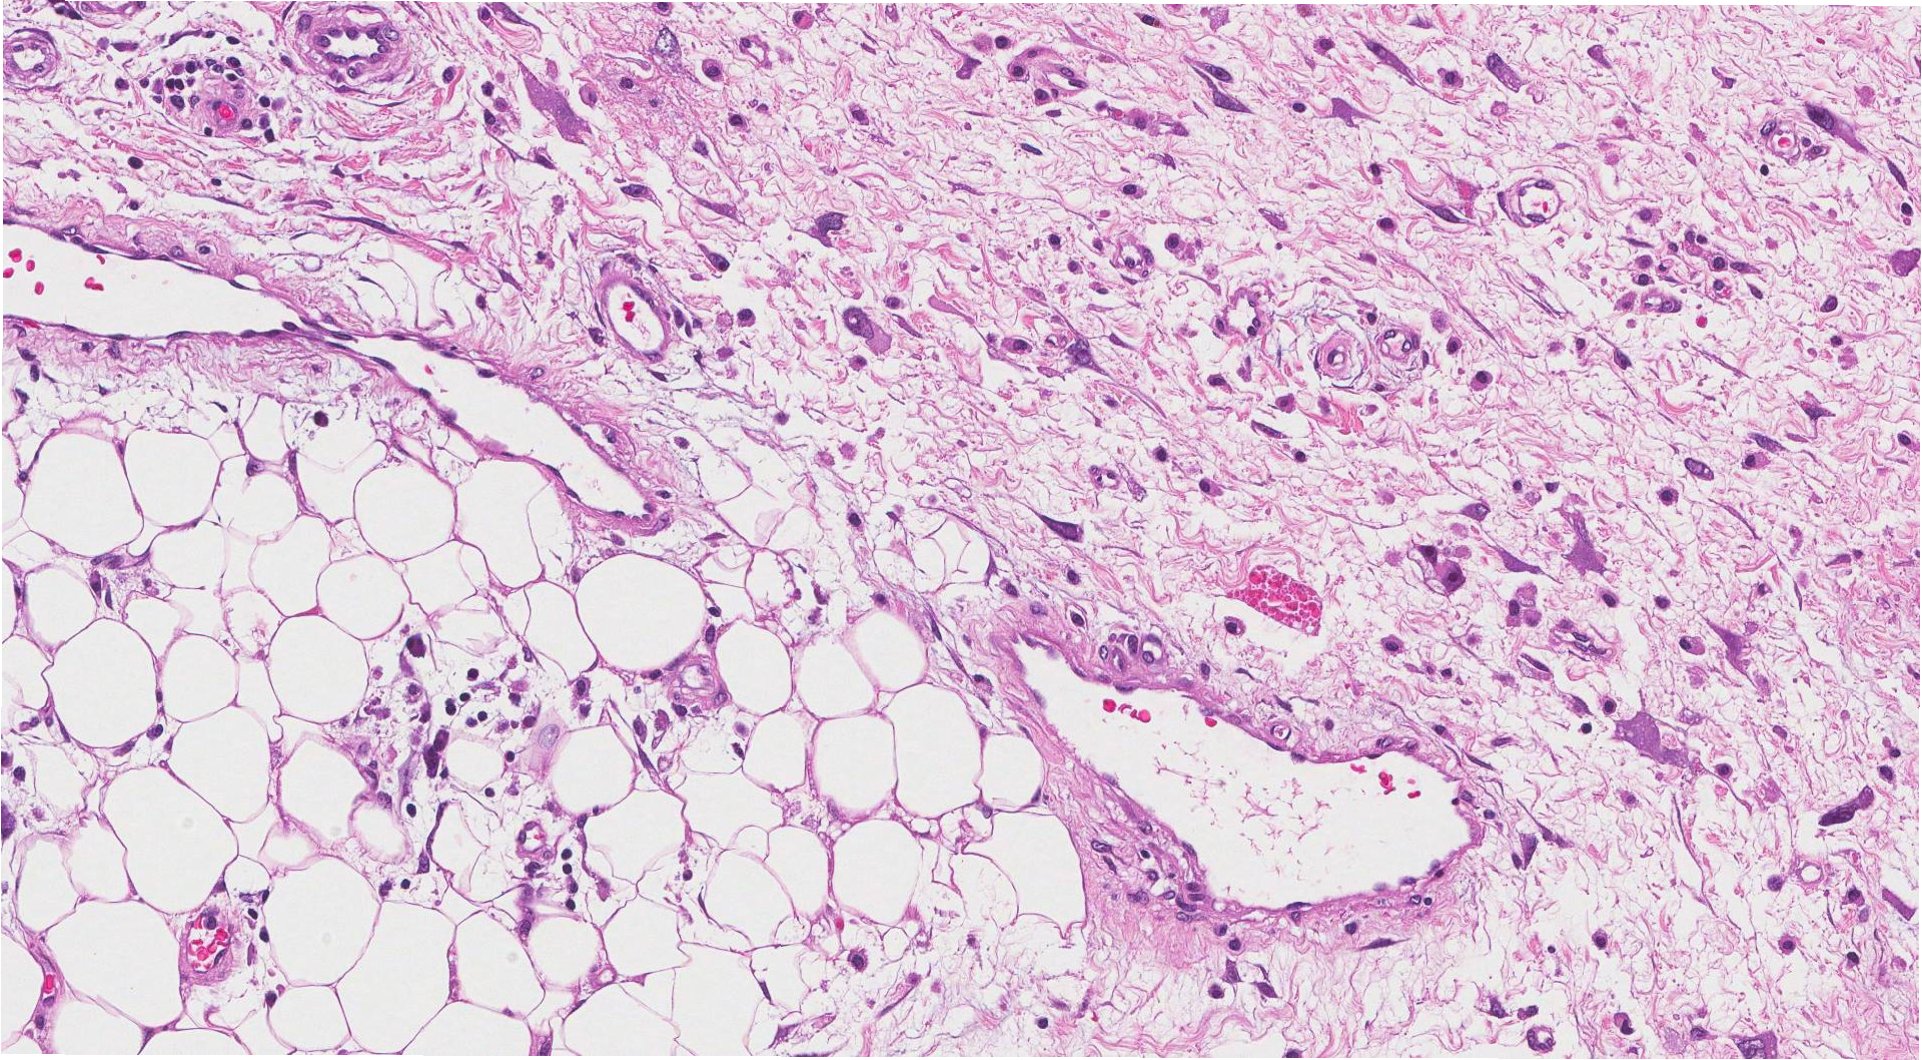

지방육종은 지방세포에서 발생하는 악성 종양으로, 전체 암의 1% 미만을 차지할 정도로 매우 드문 암입니다. 이 암은 신경과 근육 사이로 깊숙이 파고들어, 발견 시 이미 상당히 진행된 경우가 많습니다. 로라의 경우, 방사선 치료를 통해 종양 크기를 줄인 후 7시간에 걸친 절제 수술을 받았습니다. 수술 후 신경 손상으로 인해 미세한 손동작에 어려움을 겪고 있지만, 직장에 복귀하여 적응형 장비를 사용하며 업무를 이어가고 있습니다. 초기 검사에서 폐에 작은 결절이 발견되어 전이가 의심되었으나, 추가 검사 결과 과거 감염 흔적으로 밝혀졌습니다.

지방육종은 통증이 거의 없고 근육통이나 염좌와 비슷한 증상을 보여, 진단이 늦어지는 경우가 많습니다. 특히 팔다리의 근육 깊숙한 곳에서 시작되어 초기에는 통증이 거의 없어, 단순 근육통이나 노화로 오해하기 쉽습니다. 하지만 종양이 커지면서 신경과 근육을 압박하여 움직임 저하, 감각 이상, 손 기능 저하 등의 신경 증상을 유발할 수 있습니다. 미국 및 영국 가이드라인에서는 4cm 이상이거나 4주 이상 지속되는 깊은 혹에 대해 반드시 전문의 진료를 받을 것을 권고하고 있습니다.

지방육종의 진단에는 MRI와 조직 생검이 필수적입니다. 지방종과 유사하게 보이더라도 내부 구조가 불규칙하거나 성장 속도가 빠르다면 지방육종을 의심해야 합니다. 치료의 핵심은 광범위 절제술이며, 절제연이 깨끗해야 재발 위험을 낮출 수 있습니다. 종양이 크거나 신경 및 혈관을 침범한 경우에는 방사선 치료를 병행하여 종양 크기를 줄인 후 수술을 진행합니다. 폐 전이 여부를 확인하기 위해 정기적인 흉부 검사가 필요합니다.